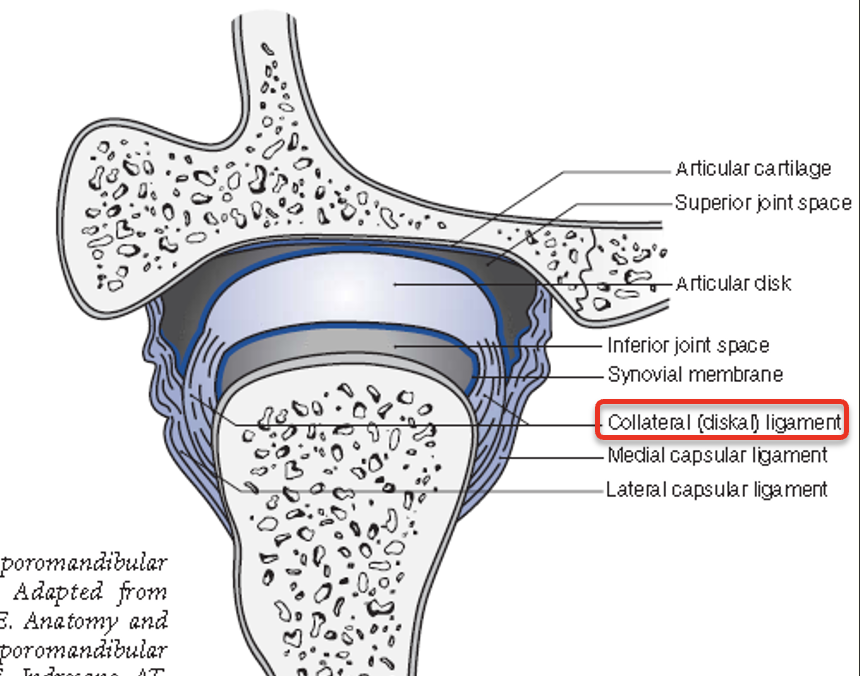

Join capsule

Joint disk

Lower division 連到 condylar neck 的 lat.,med. poles

-

Upper division 連到 Temporal bone 的 postglenoid process

collateral ligament